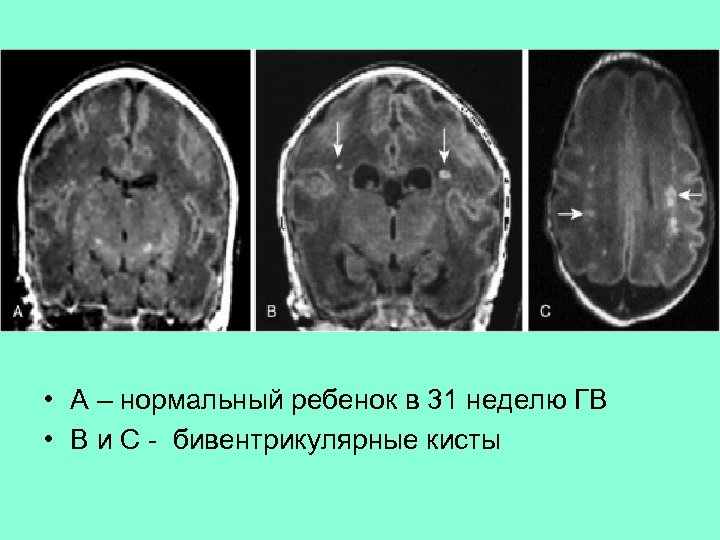

• А – нормальный ребенок в 31 неделю ГВ • В и С - бивентрикулярные кисты